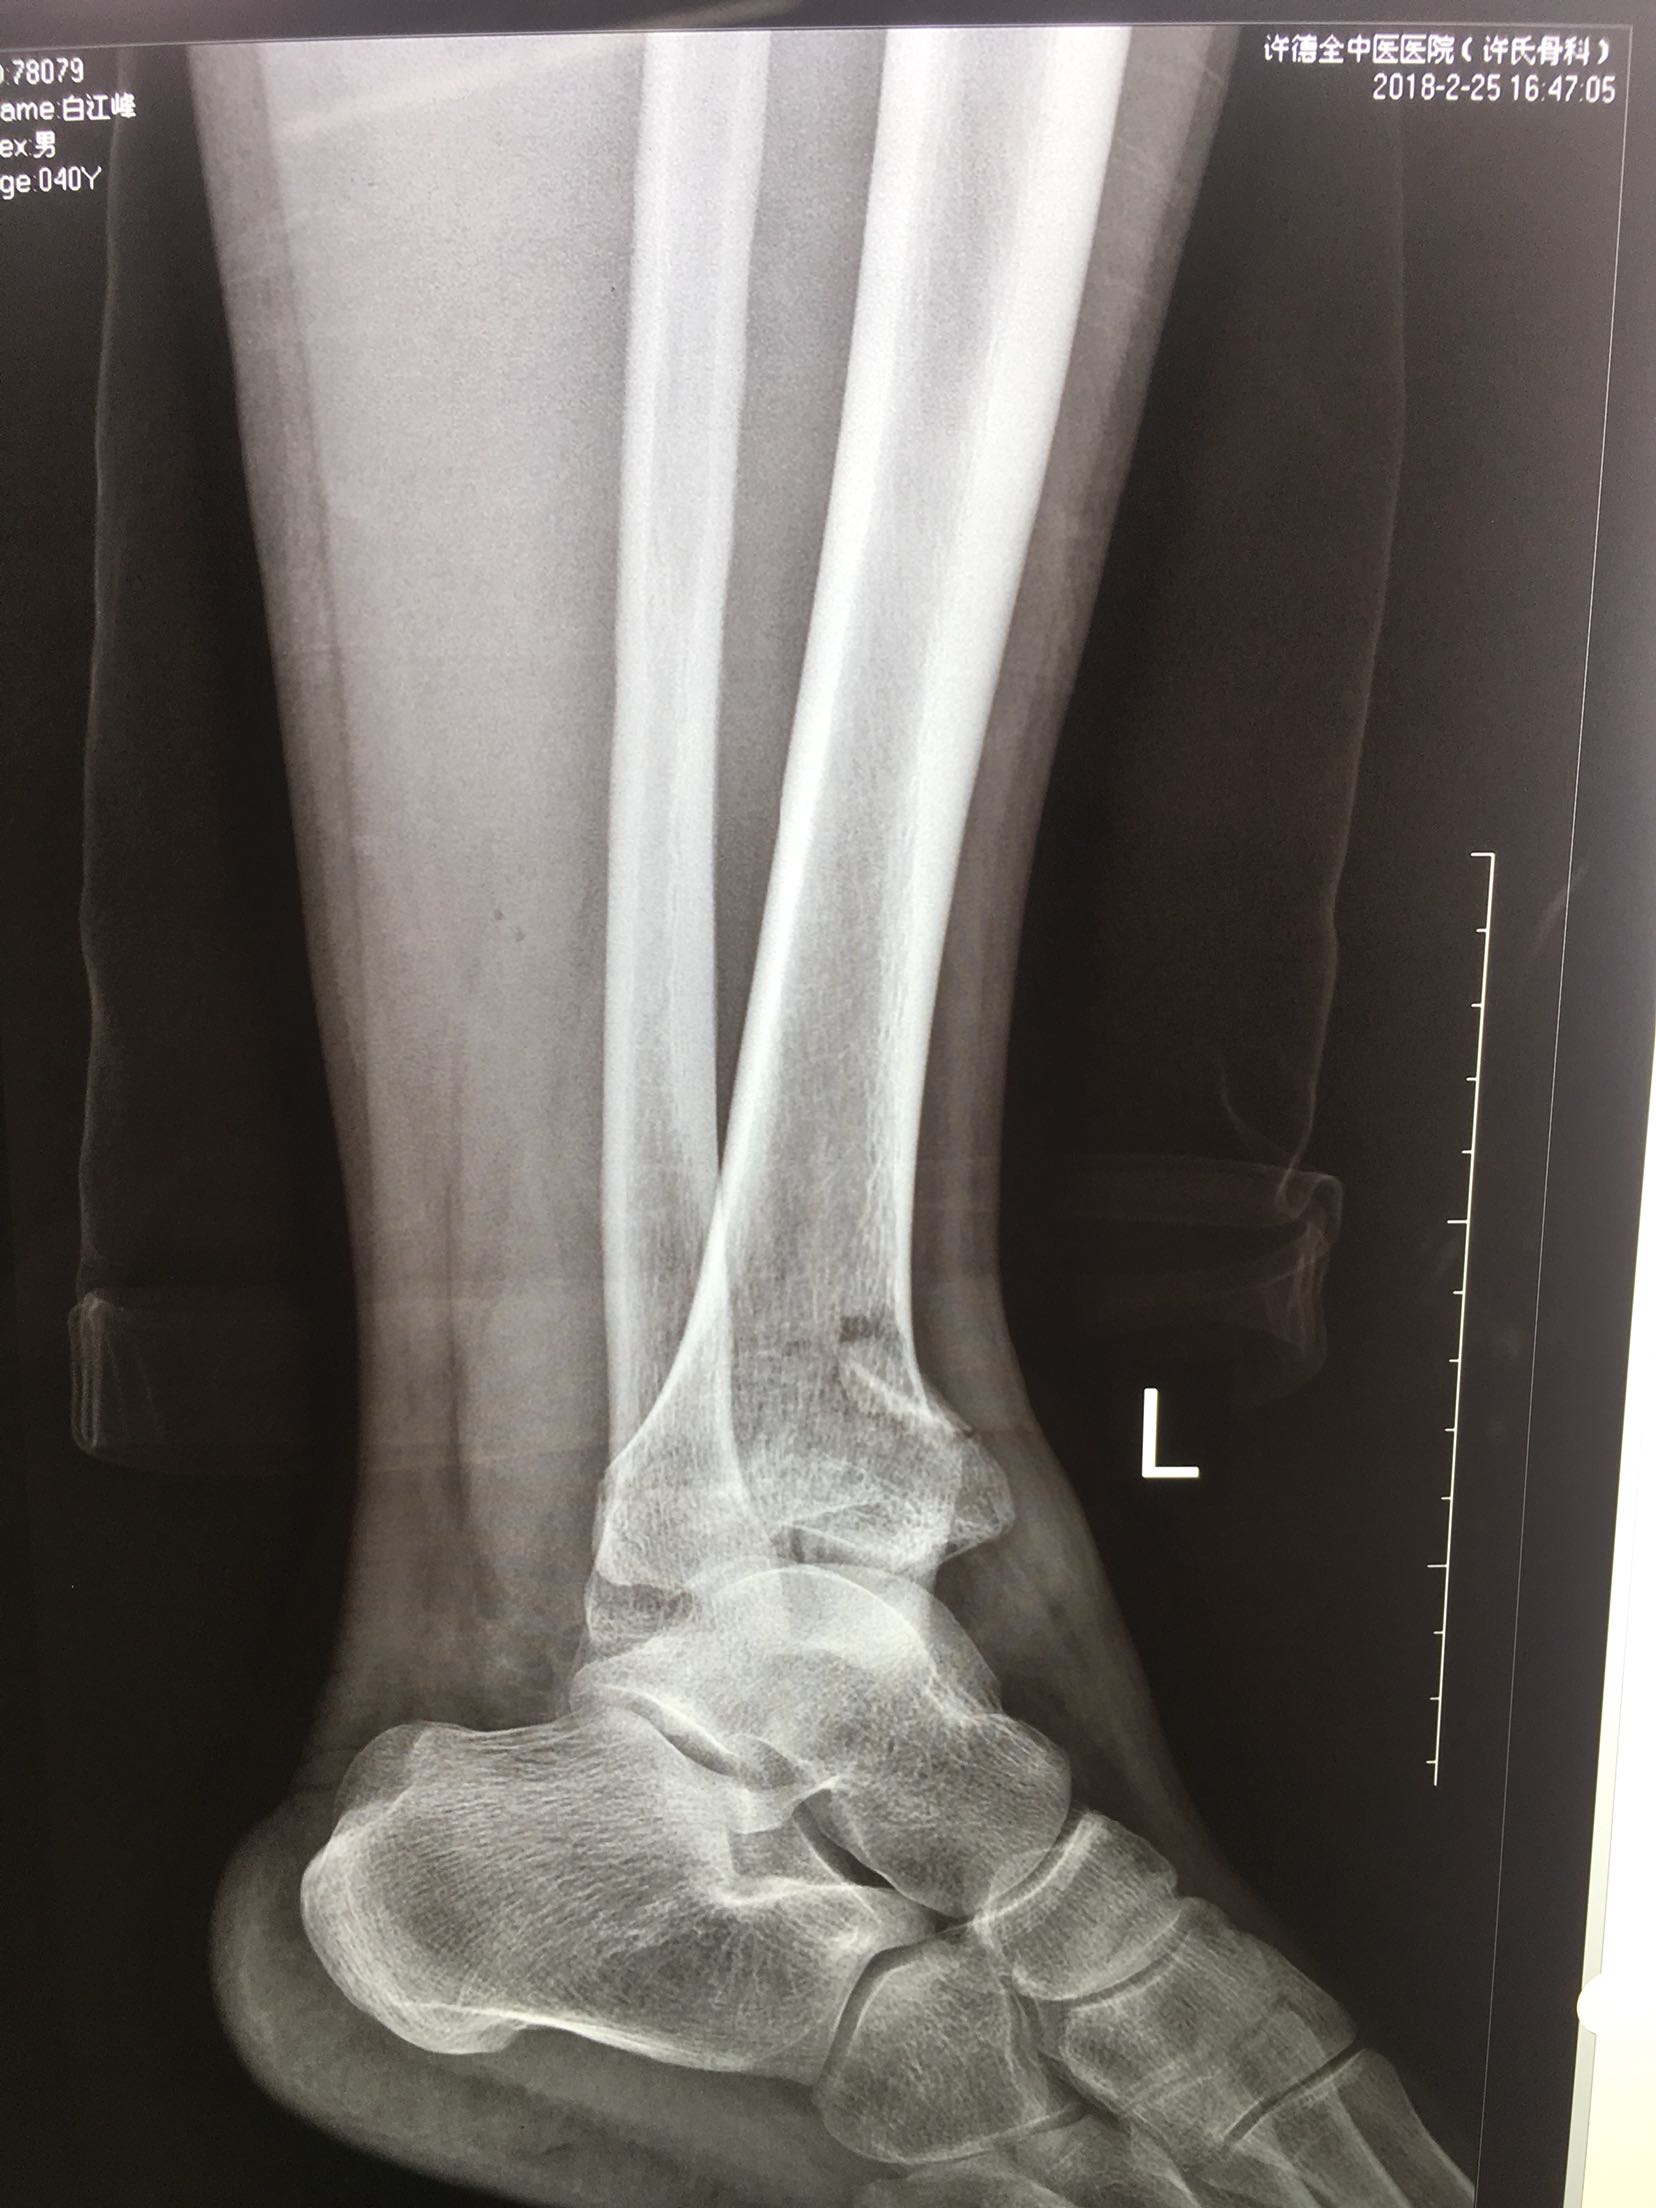

Pilon 骨折

患者,男性,41岁,坠落伤后左踝肿痛,活动受限1小时

左踝肿胀,局部皮色正常,皮温高,完整,无张力性水泡,畸形,踝关节活动受限,远端血运感觉正常。

完善检查,在腰麻下行切复内固定术,术后制动,消肿抗炎处理。